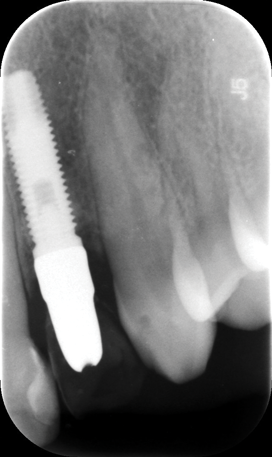

Fig 2. Placement of an implant in a young adult. A female patient had had a congenitally missing maxillary lateral incisor restored when she was 20 years old. Ten years later (Fig 2) the implant-supported restoration was in an infraocclusion state, shorter than the neighboring teeth, due to continuous skeletal growth. Radiograph (Fig 3) showed the marginal bone level of the implant was not affected.

Figure 2

Numerous clinical studies of skeletal changes and alveolar bone growth modifications around single implant-supported restorations in the esthetic zone in growing pigs and human case reports have been published.24-27 This issue has attracted particular attention in young individuals, most of whom required implant therapy due to congenital agenesis or trauma. A topic of thorough discussion among clinicians has been whether to use dental implants in young patients at all to replace missing teeth and, if so, what is the optimal age to place them with regard to possible skeletal changes that might follow. Implants become ankylosed to the bone in an identical way that an avulsed tooth behaves following late re-implantation.28 Such ankylosed teeth as well as dental implants do not adapt to eruptive processes of the surrounding skeletal growth and thus develop infraocclusion, which can severely affect esthetic appearance by the tooth or restoration being shorter than the neighboring teeth, which continue their growth (Figure 2 and Figure 3). Additionally, interproximal contact opening has been observed between the ankylosed crown and nearby natural crowns. Several in vivo experiments that examined osseointegrated implants in young populations concluded that dental implants should not be placed in young patients until their permanent dentition is fully erupted and their skeletal growth completed.29 Such recommendation was even more accentuated when the esthetic zone was involved.